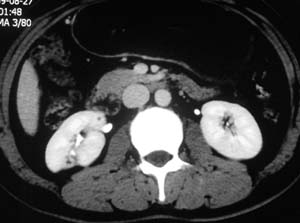

以下是引用子期在2010-3-19 20:47:00的发言:[br]血管畸形的ct增强应该有明显强化,本例并不相符合。本例双肾局部的略低密度影,累及肾盂,局部皮质明显变薄、内陷,增强扫描有轻度的强化,应考虑为炎性病变,患者为年轻男性,累及双肾的感染以结核较常见,可以没有明显的临床症状,尿中有时候也并不能查出什么;肾脓肿常有明显感染中毒症状,本例不符,另外一般的肾盂肾炎或肾小球肾炎通过小便就可确诊,其它还不能排除的是黄色肉芽肿性肾盂肾炎,然而单凭ct一般也很难鉴别。